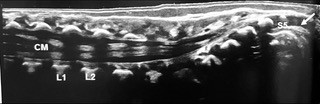

Pediatric sonography uses real time imaging with sound waves to diagnose conditions in organs and blood vessels. The sound waves allow the sonographer to clearly see many parts of the body, such as the abdomen, spine, hips, breasts, pelvis, scrotum, and thyroid. Pediatric ultrasound is a great diagnostic tool for children because there is no exposure to radiation and it is painless.